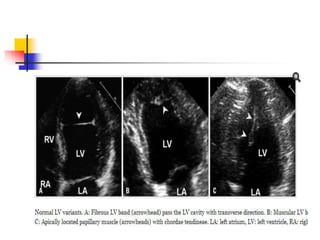

 false tendons are fibromuscular structures crossing

the LV cavity.

 LV bands may pass between papillary muscles, from

papillary muscle to the ventricular septum, between

free walls, or from free wall to interventricular septum,

in contrary to true chordae tendineae connecting

papillary muscle and mitral valve leaflets.

 False tendon is found up to 55% in normal hearts by

autopsy .

 In echo, LV bands appear as string-like thin bands

passing LV cavity , which may be transverse,

longitudinal, or sagittal, and single or multiple.

 location, direction, length and thickness of LV bands

may vary depending on their embryonic origin of

inner cardiac muscle layer and contents.

 Muscular bands become shorter and thicker in

systole, and vice versa in diastole.

 Fibrous bands become straight and taut in diastole,

and vice versa in systole.

 Off-axis images demonstrating the overall length of

bands, normal LV structures on both ends, and

constant motion during cardiac cycle are the key

features.

 False tendon located near LV apex may be confused

for mural thrombus particularly in images of true LV

apex being not completely visualized.

Papillary muscles

 vary in shape, thickness, & location in LV wall.

 More than one belly is observed in up to 50% .

 Accessory papillary muscle may be confused for

pathologic structures such as LV thrombus or

papillary muscle tumors when it arises from an

unusual location.

 presence of LV band is strongly indicative of the

accessory papillary muscle instead of pathologic

entity.

 Normally contractile adjacent LV wall help to exclude

the mural thrombi.